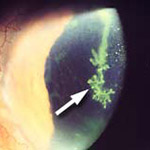

Flashes and Floaters

Tiny bits of vitreous gel or cells that cast shadows on the retina.